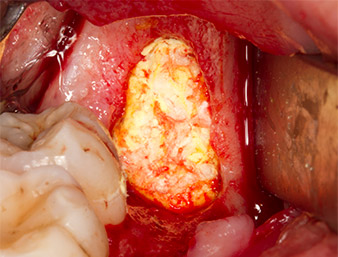

Um autogenes Material für die spätere Wundversorgung zu gewinnen, wurden mit einem piezochirugischen Instrument (Piezomed B5) gesunde Knochenspäne aus der Umgebung des Wurzelrests gewonnen (Abb. 5).

Das autogene Gewebe wurde mit dem schaufelförmigen Arbeitsteil des Instruments entnommen und bis zur weiteren Verwendung in physiologischer Kochsalzlösung aufbewahrt (vgl. Abb. 13).

Nachfolgend wurde das autogene Knochengewebe (Abb. 13) in die Alveole und den umliegenden Knochendefekt eingebracht (Abb. 14). Kollagenvlies bedeckte als Schutz für den freiliegenden Nerv die Knochenspäne bis auf Knochenniveau (Abb. 15).